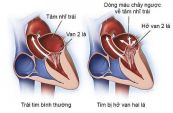

Tìm hiểu về bệnh Sa van hai lá cùng eLib sẽ cho bạn biết về triệu chứng, nguyên nhân, nguy cơ và tham khảo cách điều trị bệnh hiệu quả.